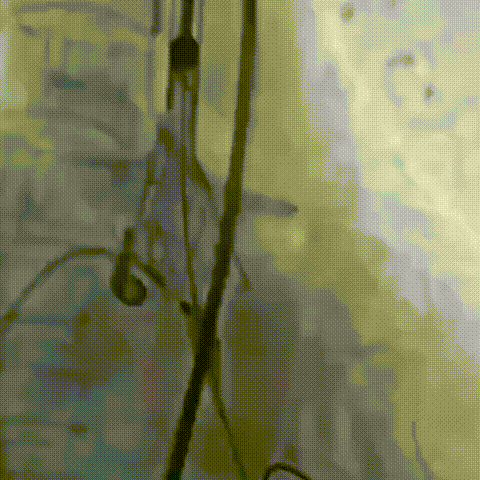

工作位冠脉球扩

瓣膜释放2/3同时发现患者血压降低,立即释放冠脉支架

术中TaurusElite瓣膜系统优异的输送性能,保障了术中轻松过弓、顺利跨瓣。钟志雄院长团队通力配合、精准释放,充分利用TaurusElite可回收功能,在瓣膜释放至2/3时,多角度评估瓣膜植入深度、锚定力以及冠脉灌注情况。此时患者血压偏低,根部造影评估后,考虑左主干开口受限冠脉灌注不全导致。随即释放预埋支架,行烟囱支架技术保护冠脉。完成冠脉保护后,确认瓣膜植入深度合适、锚定力稳定,故缓慢逐个脱钩,进行瓣膜释放。